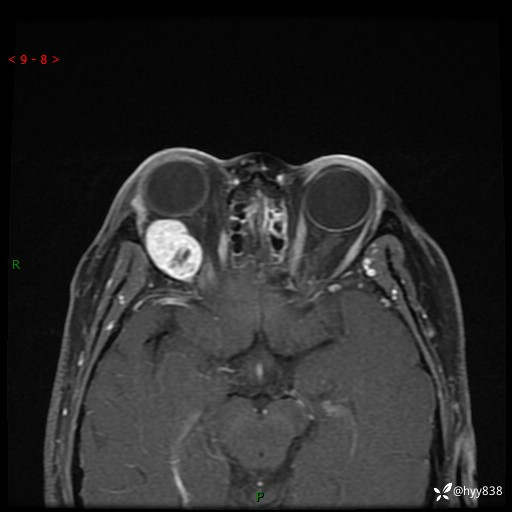

老年女性,右眼球突出1月。说说鉴别诊断,看谁第一个秒---(有结果)

主诉:发现右眼球突出1月余

简要病史:患者于1月前无明显诱因发现右眼球突出,偶感磨痛、眼胀,无视力下降,无头痛,恶心呕吐等不适。10天前就诊于当地县人民医院就诊,完善头颅ct检查,诊断为右侧眼眶肿物,建议患者上级医院进一步治疗,患者因个人原因拒绝。拟行手术,来我院就诊,门诊行相关检查后以“右眼眼眶肿物”收入院。 患病以来,患者精神饮食睡眠尚可,大小便如常、体重无明显改变。

辅助检查:MRI

临床诊断:眼眶肿物

眼眶MRI平扫+增强